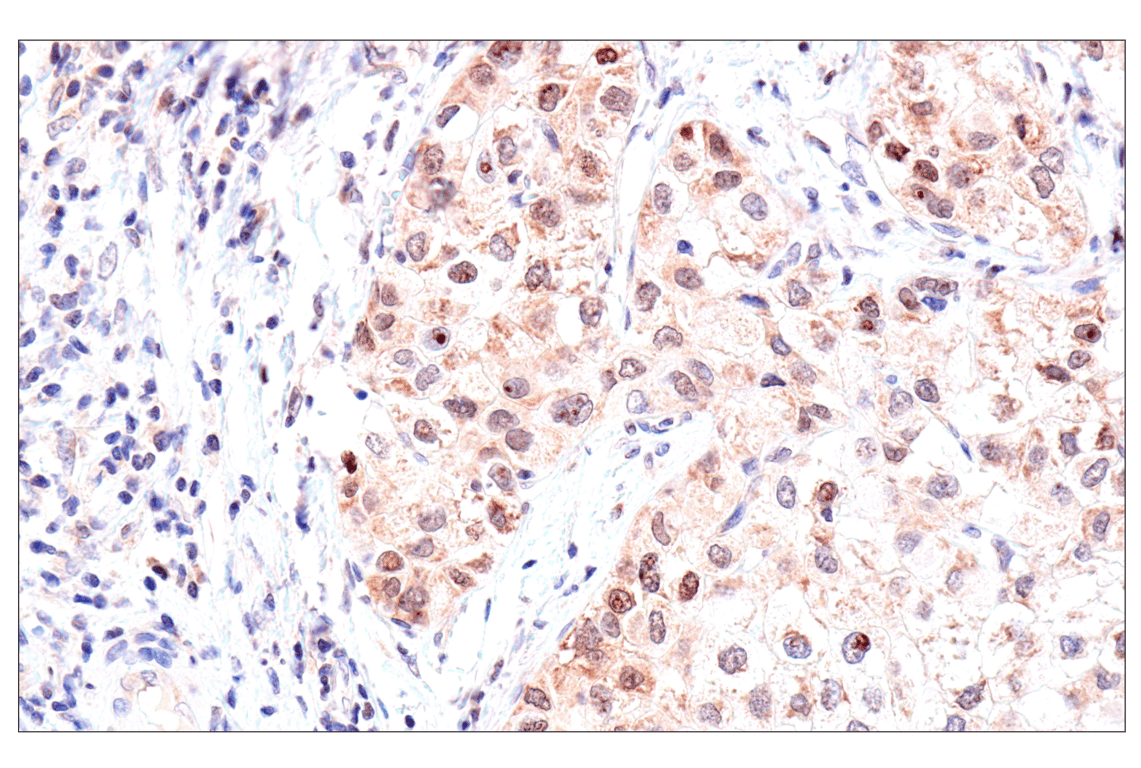

Immunohistochemical analysis of paraffin-embedded human oropharyngeal squamous cell carcinoma using ADAR1 p150 Isoform (E6U1U) Rabbit mAb.

Immunohistochemistry Image 2: ADAR1 p150 Isoform (E6U1U) Rabbit Monoclonal Antibody